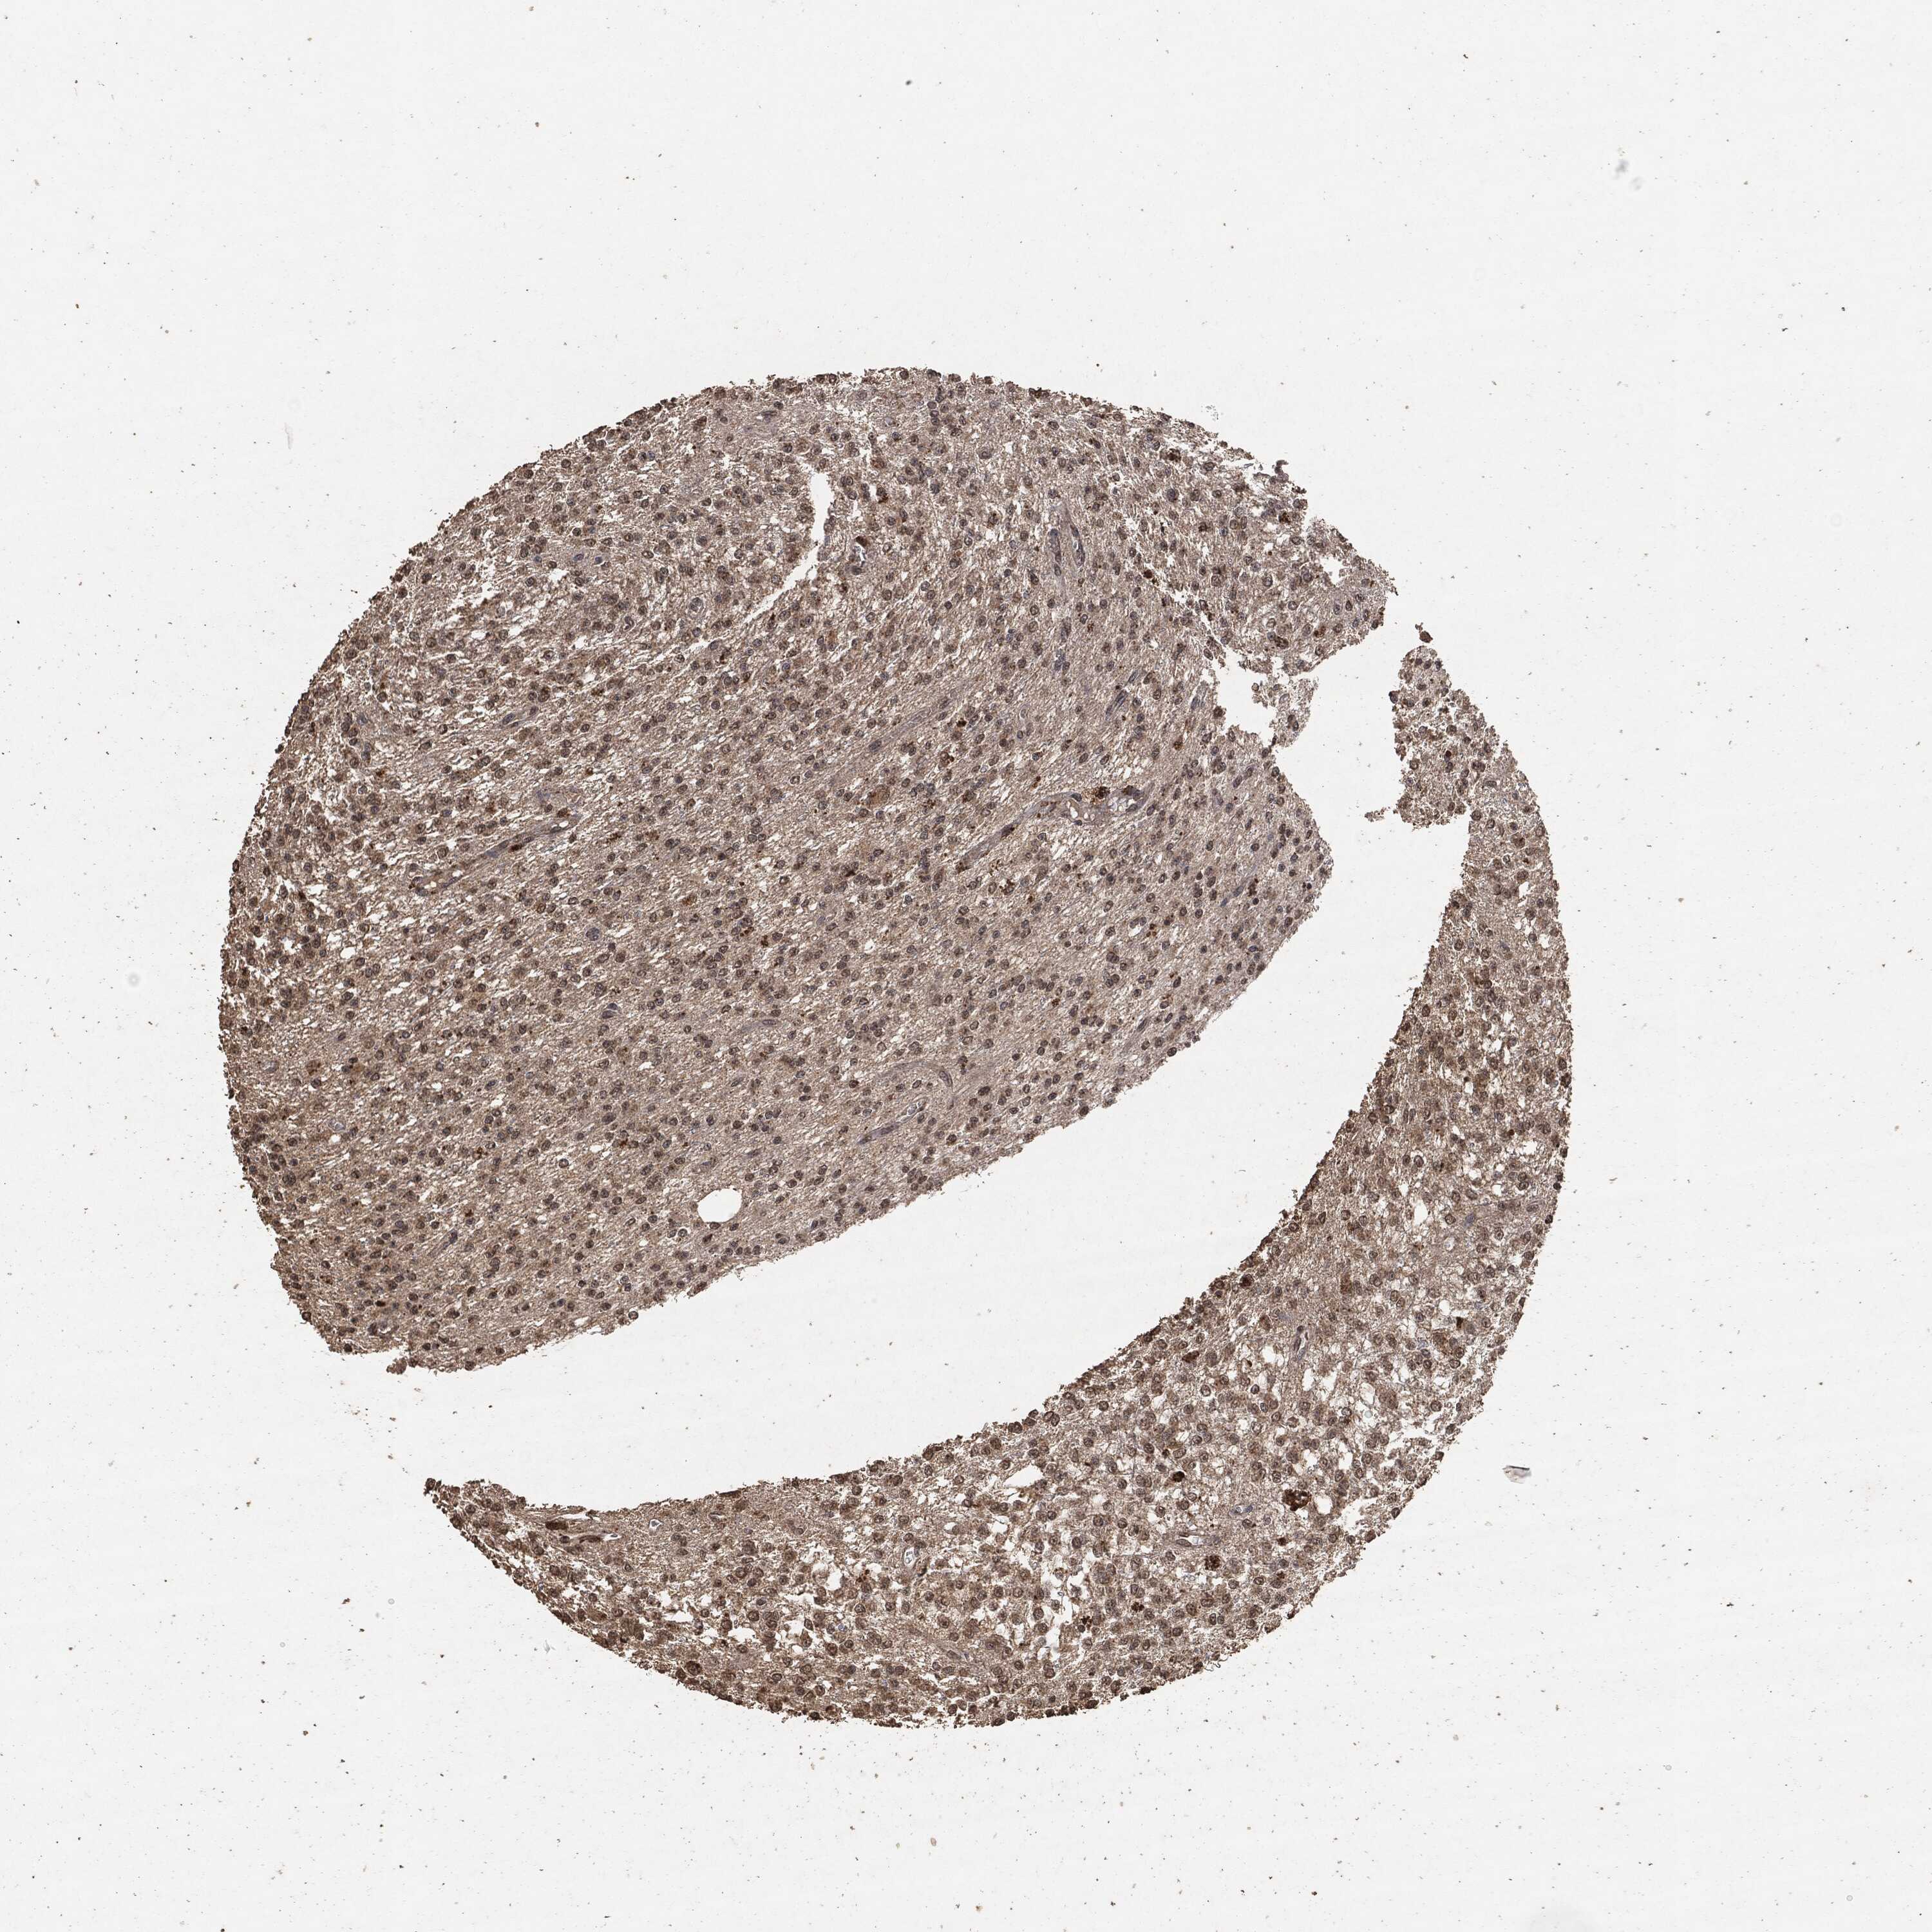

GLIOMA - Protein expressioni

A mouse-over function shows sample information and annotation data. Click on an image to view it in a full screen mode. Samples can be filtered based on level of antibody staining by selecting one or several of the following categories: high, medium, low and not detected. The assay and annotation is described here.

Note that samples used for immunohistochemistry by the Human Protein Atlas do not correspond to samples in the TCGA dataset.

Antibody stainingi

Antibody staining in the annotated cell types in the current human tissue is reported as not detected, low, medium, or high, based on conventional immunohistochemistry profiling in selected tissues. This score is based on the combination of the staining intensity and fraction of stained cells.

Each image is clickable and will lead to virtual microscopy that enables deeper exploration of all samples and also displays staining intensity scores, fraction scores and subcellular localization as well as patient and tissue information for each sample.

Glioma, malignant, High grade

Glioma, malignant, Low grade

Glioma, malignant, NOS